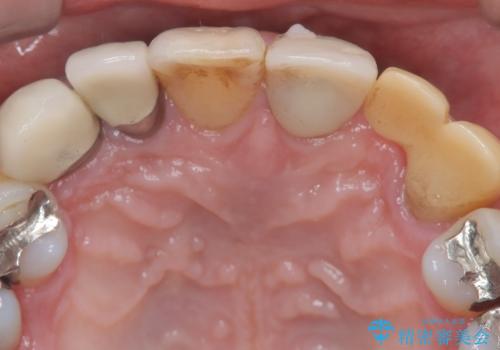

左上1番目~3番目にかけてブリッジの仮歯が入った状態で来院された患者さんで、左上3に縁下カリエスを認め抜歯してインプラントか牽引(エクストリュージョン)を行うか、歯肉根尖側移動術を行うか選択いただき牽引の後補綴処置を行うこととしました。

左上3の牽引を1か月半ほど行った後、補綴治療を行っています。

両支台歯とも根尖病巣は認められなかったため、ファイバ-コアからのやり替えとしました。